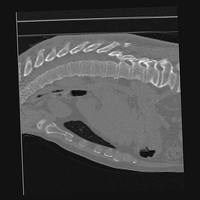

Exp. 3: Adult thorax data: To show the versatility of our approach we also apply it to adult thorax scans. For this experiment no organ specific training is performed but the whole volume is used. We evaluate reconstruction performance similar to Exp. 1 and prediction performance when is projected on an external plane, comparable to X-Ray examination using C-Arms. The latter provides insights about our method’s performance when applied to interventional settings in contrast to motion compensation problems. 60 healthy adult thorax scans were randomly selected, 51 scans used for and nine scans used for . Each scan is intensity normalised and resampled in a volume of with spacing . Using the Fibonacci sampling method, 25 sampling plane of size , evenly spaced between -50 and +50, were rotated over 500 normals. Training took approximately 20 hours for 60 epochs. Fig. 4c shows an example reconstruction result gaining 28dB PSNR with additional SVR. prediction takes approx. 20 ms/slice for this data.

0..5.3 Exp. 3:

We replicated the experiment on adult thorax data without specifically segmented organs. This approach was applied to CT acquisition, shown in Fig 13 and 14, as well as Digitally Reconstructed Radiographs generated using Siddon-Jacobs Ray Tracing shown in Fig. 16.